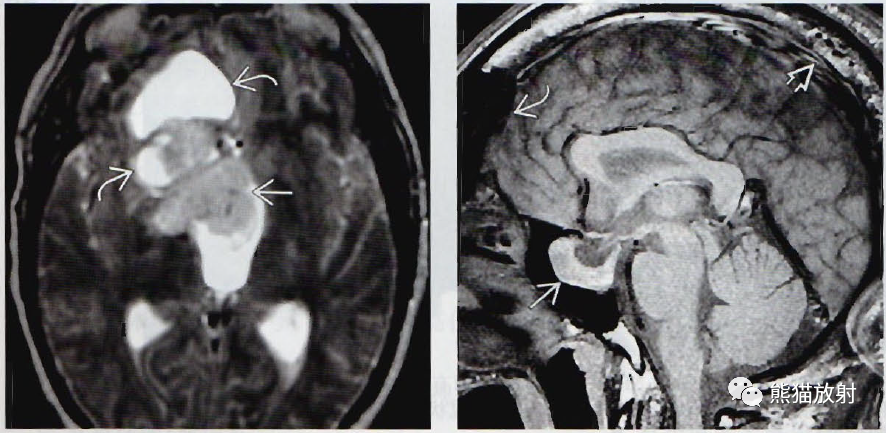

(左) 轴位T2WI MR显示大腺瘤伴高信号囊肿。这可能是扩大的血管周围间隙中阻塞的间质液体。

(右)一例长期肢端肥大症的30岁男性患者,矢状位T1WI MR显示垂体大腺瘤侵及蝶窦(直箭)。请注意颅骨(空箭)增厚,额窦(弯箭)扩大。